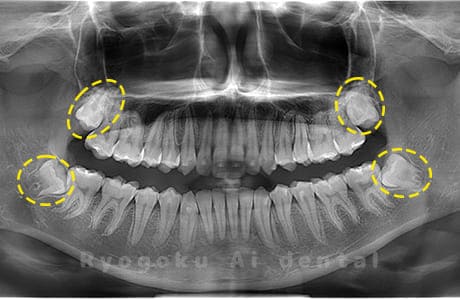

Case04

-

- 原因

- 上顎の親知らず、下顎の水平埋伏の親知らず

- 治療内容

- 上顎の親知らず、下顎の水平埋伏の親知らずを抜歯したケースです。

<リスク・副作用>

手術後は痛み、腫れ、痺れなどの副作用が生じる場合があります。